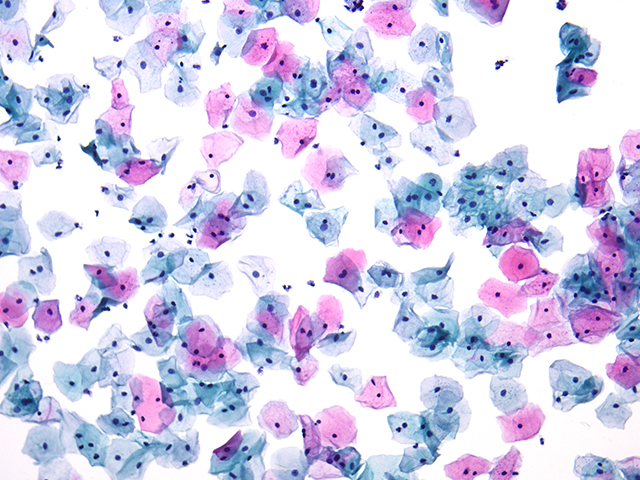

近期,有客戶針對組織切片拍照觀察提出了特定需求。其主要應用集中在病理和毒理生物組織切片的觀察拍照,因而急需一台帶成像功能的生物顯微鏡。這要求顯微鏡能夠清晰地呈現組織切片的微觀結構,準確捕捉每一個(ge) 關(guan) 鍵細節,以便為(wei) 後續的分析診斷提供可靠依據。

明美提出了生物顯微鏡ML31 搭配高像素攝像頭解決(jue) 方案生物顯微鏡ML31 具備良好的光學性能,能夠提供清晰、穩定的成像基礎。而與(yu) 之搭配的大靶麵高像素相機更是如虎添翼,在明場拍照時可以呈現出清晰的圖像效果。